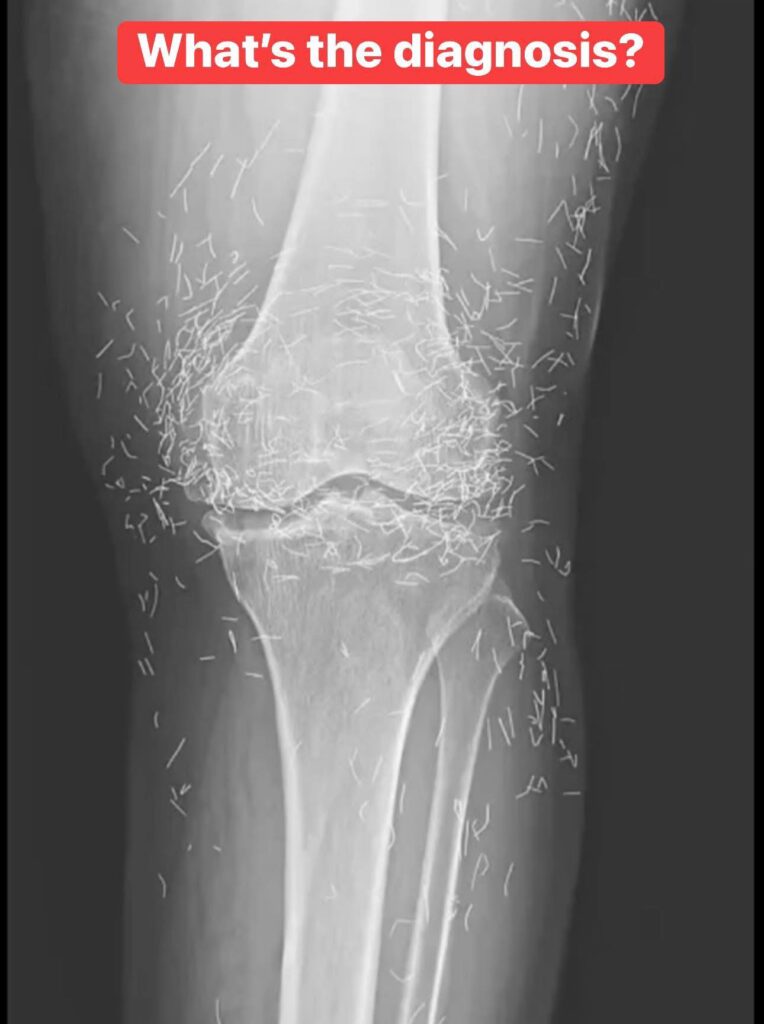

When a 65-year-old South Korean woman went in for knee pain, doctors weren’t expecting to strike gold. But that’s exactly what they found.

So she turned to acupuncture, according to a case published in the New England Journal of Medicine.

Acupuncture, a centuries-old alternative treatment, involves inserting needles into the body at specific points to relieve pain or treat illnesses. In this case, the needles— presumably made of gold — were intentionally left in her knees for continued stimulation.

He also warned that embedded needles can complicate X-ray readings. “The needles may obscure some of the anatomy,” Guermazi said in 2013.